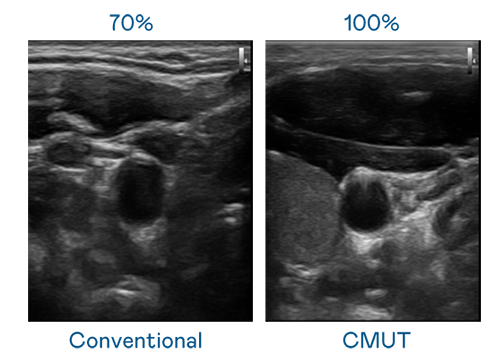

CMUT 技术是一种用电容式微机电元件来产生超音波讯号的技术。与传统 PZT 压电式技术相比,CMUT 频宽增加 30%,更宽频的超音波讯号让影像解析度大幅提升,是实现高影像品质医疗超音波扫描、促进精准医疗发展的关键技术。

超音波影像的解析度高低,首先取决于探头能发出的讯号频宽。东升国际官网入口 CMUT 可提供高清晰的超音波讯号,提供高频宽、高灵敏度、影像纹理细节更高的超音波影像,协助医护人员缩短影像判读时间及利用精准的医疗影像进行诊断。